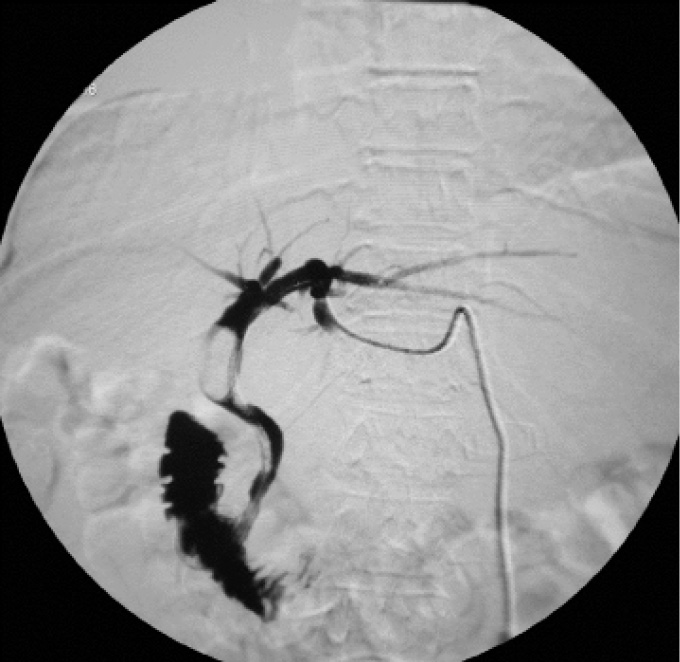

В октябре 2019 г. у пациентки появилась жалобы на желтушность кожного покрова и слизистых, общую слабость, умеренную, ноющую боль в эпигастральной и правой подреберной областях, повышение температуры тела до фебрильных цифр. Больная была госпитализирована с диагнозом «механическая желтуха, холангит». Попытки эндоскопического редренирования желчных протоков оказались безуспешны. При выполнении чрескожной чреспеченочной холангиографии в месте слияния культи правого долевого и левого долевого протоков с переходом на гепатикохоледох определялась злокачественная стриктура (Bismuth II). Контрастный препарат в гепатикохоледох, двенадцатиперстную кишку не поступал. Выполнено чрескожное чреспеченочное наружновнутреннее дренирование желчных протоков единственной левой доли печени. Установлен желчный дренаж диаметром 8,5 F (рис. 1).

Рис. 1. Чрескожное чреспеченочное наружновнутреннее дренирование желчных протоков единственной левой доли печени